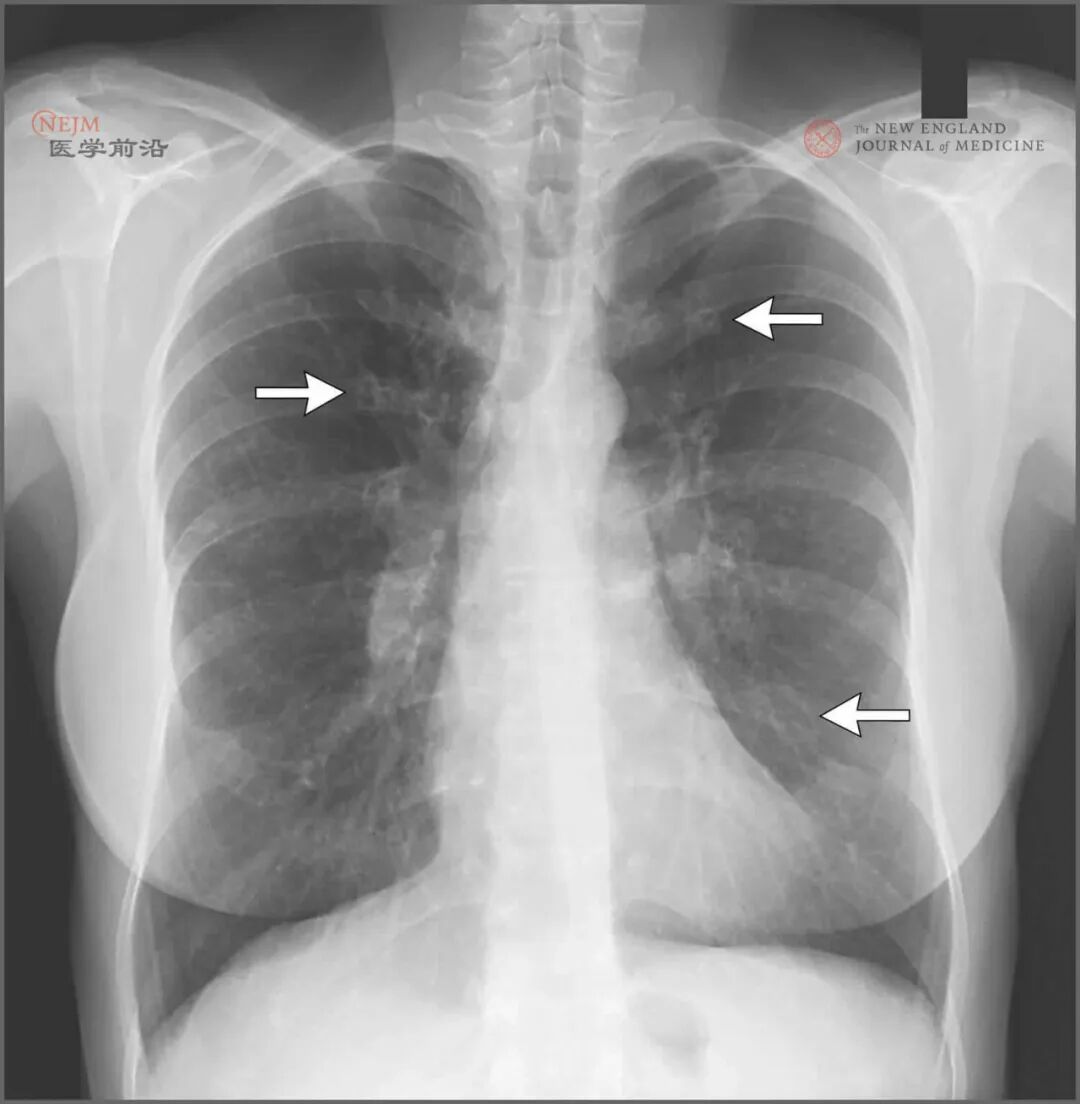

患者有长期进行性肺病史,伴有累及上呼吸道和下呼吸道的反复感染,胸部CT检查可见重度支气管扩张;这些发现均符合囊性纤维化诊断。虽然囊性纤维化通常在年轻时发病,但已发现了接近2,000种CFTR突变,每种导致不同程度的氯离子运输减少。汗液氯离子检测常用于明确诊断;氯离子水平超过60 mmol/L高度提示囊性纤维化。这名患者的汗液氯离子检测显示氯离子水平为40~45 mmol/L,这一结果提示CFTR功能部分存在,不能明确诊断。确定囊性纤维化诊断的下一步是鉴定CFTR突变。这名患者的遗传学检测显示,氨基酸508的苯丙氨酸缺失(Phe508del),1152的组氨酸被天冬氨酸取代(D1152H)。这些突变的发现明确了该患者囊性纤维化的诊断。囊性纤维化的治疗主要为综合治疗,包括通过机械和药物疗法(胸部物理治疗、吸入型人重组dornase alfa治疗、给予吸入型高渗盐水)清理呼吸道、对胰腺功能不全患者进行胰酶替代治疗、营养补充、感染抑制性抗生素治疗以及早期发现肺部状况恶化。通过在囊性纤维化专业治疗中心给予这些治疗,中位生存期从2000年的33.3年延长至2015年的41.7年。虽然该患者自诊断以来严格遵循了这些治疗,但她的肺功能仍稳定下降。促进肺功能下降的显著因素是持续的脓肿分枝杆菌感染。患者被诊断为囊性纤维化之后,她在本院接受了脓肿分枝杆菌感染治疗。患者完成了6个月疗程的抗生素治疗,包括利奈唑胺、阿米卡星和克拉霉素。治疗并发了耳鸣和重度周围神经病。患者完成这一疗程后,其良好健康状况保持了数月,但随后因发热、咳嗽和胸部X线片上新的气腔阴影到第三家医院就诊。医师给予其万古霉素和哌拉西林-他唑巴坦经验治疗;咳嗽减轻,但发热持续。由于持续发热,在第三家医院进行了视频辅助胸腔镜活检。第三家医院的组织学切片检查(图3)显示组织学特征高度符合囊性纤维化诊断。在培养物中再次分离出脓肿分枝杆菌。![]()

图A显示多灶性脓肿形成。图B显示化脓性坏死。图C显示多个囊性支气管扩张病灶伴有致密性慢性炎症。图D显示反应性鳞状上皮化生和黏液脓性碎屑。图E显示支气管扩张伴致密纤维化,以及气道闭塞区域。图F显示相关的肉芽肿性炎症。这些特征最符合囊性支气管扩张并发非典型分枝杆菌感染,患者特征符合囊性纤维化。